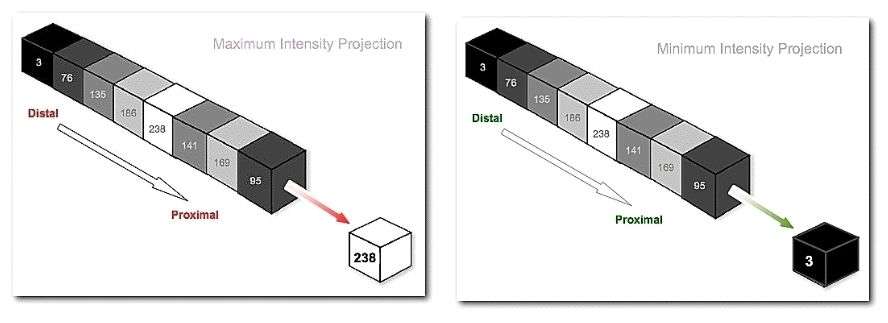

The first two images in the second row show the result of what are called a Maximum Intensity Projection (MIP) and a Minimum Intensity Projection (MinIP), respectively. A MIP evaluates each voxel along each line of voxels through the volume to determine the maximum voxel value and forms an image using the values so determined for each line. A MinIP uses the minimum voxel values, as illustrated in the following figure: